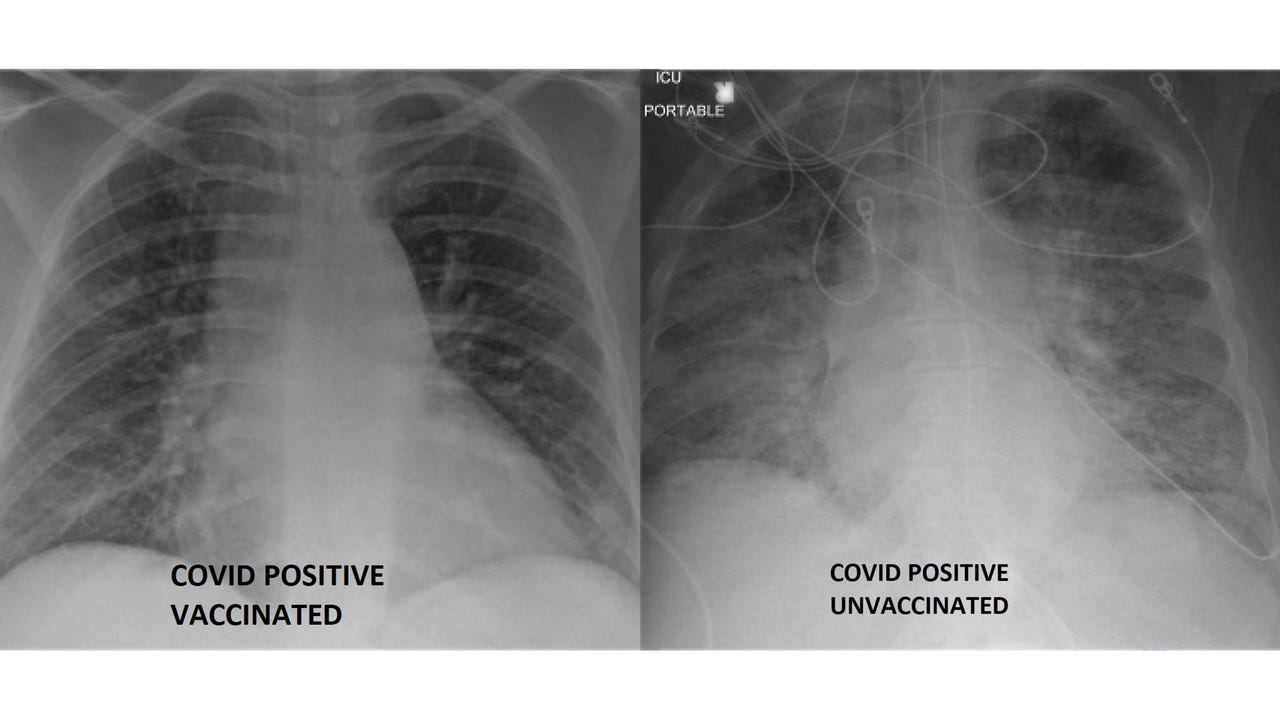

The doctor could not share specific health history regarding the two X-ray cases to protect patient information, but noted how the X-ray of the unvaccinated individual is more clouded in white. This indicates "more advanced or significant lung disease" that could be the result of a viral infection, a bacterial infection or even fluid on the lungs, Kamel said.

By contrast, Kamel explained how the vaccinated patient’s X-ray image has more black area — which shows lungs while they are filled with air. The patient is what’s known as a rare "breakthrough" case, or when a fully vaccinated person gets infected with the virus.

Lung X-rays provided by SSM Health Saint Louis University Hospital show a COVID-19 patient who was fully vaccinated (L), alongside a COVID-19 patient who was not vaccinated (R). (Photo via SSM Health Saint Louis University Hospital)